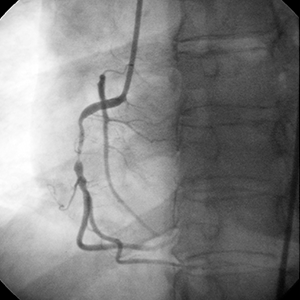

• Baseline angiography showed no significant disease in the left coronary system

• Right coronary artery (RCA) presented a high grade stenosis with a long proximal segment of disease

• Left ventricle function was normal